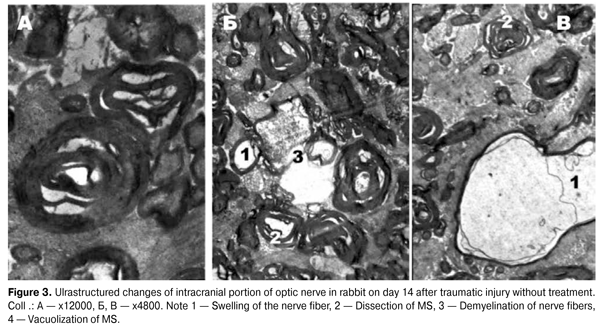

According to morphometry, a decrease in MNF area (p = 0.006972) alongside with a statistically significant increase in the g index (p = 0.000423) in intracranial portion of the right optic nerve, has been observed in the treated group compared to the injured one, indicating active processes of remyelination of these fibers. The electron-diffraction patterns of optic nerves in the group without treatment (Fig. 3) show that fibers’ axoplasm had a significant swelling of the MS of low electron density, and was vacuolated. The mitochondria were almost absent, and those that remained were swollen with enlightened matrix, deformed and partially destroyed by cristae. Strips of myelin were often chaotic, moving away from each other, having a wavy motion. All this, according to the studies, may indicate a disruption of axonal transport along the axial cylinders [6, 16, 17], caused by swelling of MS and can be interpreted as a periaxonal degeneracy. MNFs were often observed with symptoms of demyelination, specific manifestations of which was a deep disruption of the myelin sheath and a separation of myelin fragments that were freely located in the axoplasm or the cytoplasm of Schwann cell, indicating a disruption of the energy and protein metabolism [5, 8, 19].